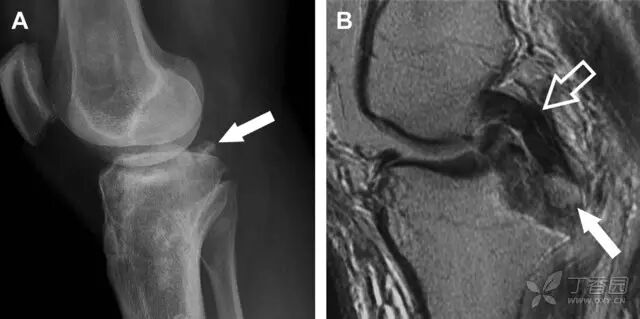

图 3 胫骨后外侧碎片骨折

A 正位片示胫骨后外侧处可见一压缩骨折的小碎片(方框)。这是胫骨撞击股骨外侧髁旋转移位时所致。B 另一位患者的 MRI 矢状位 T1 加权像示胫骨后外侧骨折碎片(箭头)。